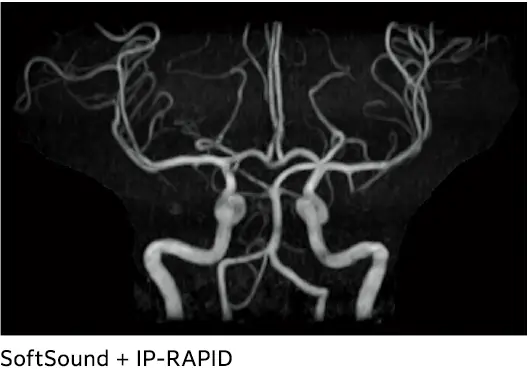

IP-RAPID, geleneksel görüntüleme yöntemleriyle karşılaştırıldığında, görüntü kalitesini korurken tarama sürelerini %60`a kadar azaltan, iteratif işleme kullanan bir yüksek hızlı görüntüleme teknolojisidir.

SoftSound ile sessiz inceleme

MRI akustik gürültüsünü azaltmak için çeşitli teknolojiler mevcuttur. Ancak, akustik gürültünün azaltılması genellikle görüntü kalitesini olumsuz etkiler ve tarama süresini uzatması nedeniyle rutin inceleme için uygun değildir. Diğer yaklaşımlar özel donanım gerektirir. SoftSound gürültü azaltma teknolojimiz, herhangi bir özel donanım olmadan görüntü kalitesini ve tarama süresini koruyarak akustik gürültüyü %96'ya*2 kadar azaltır.